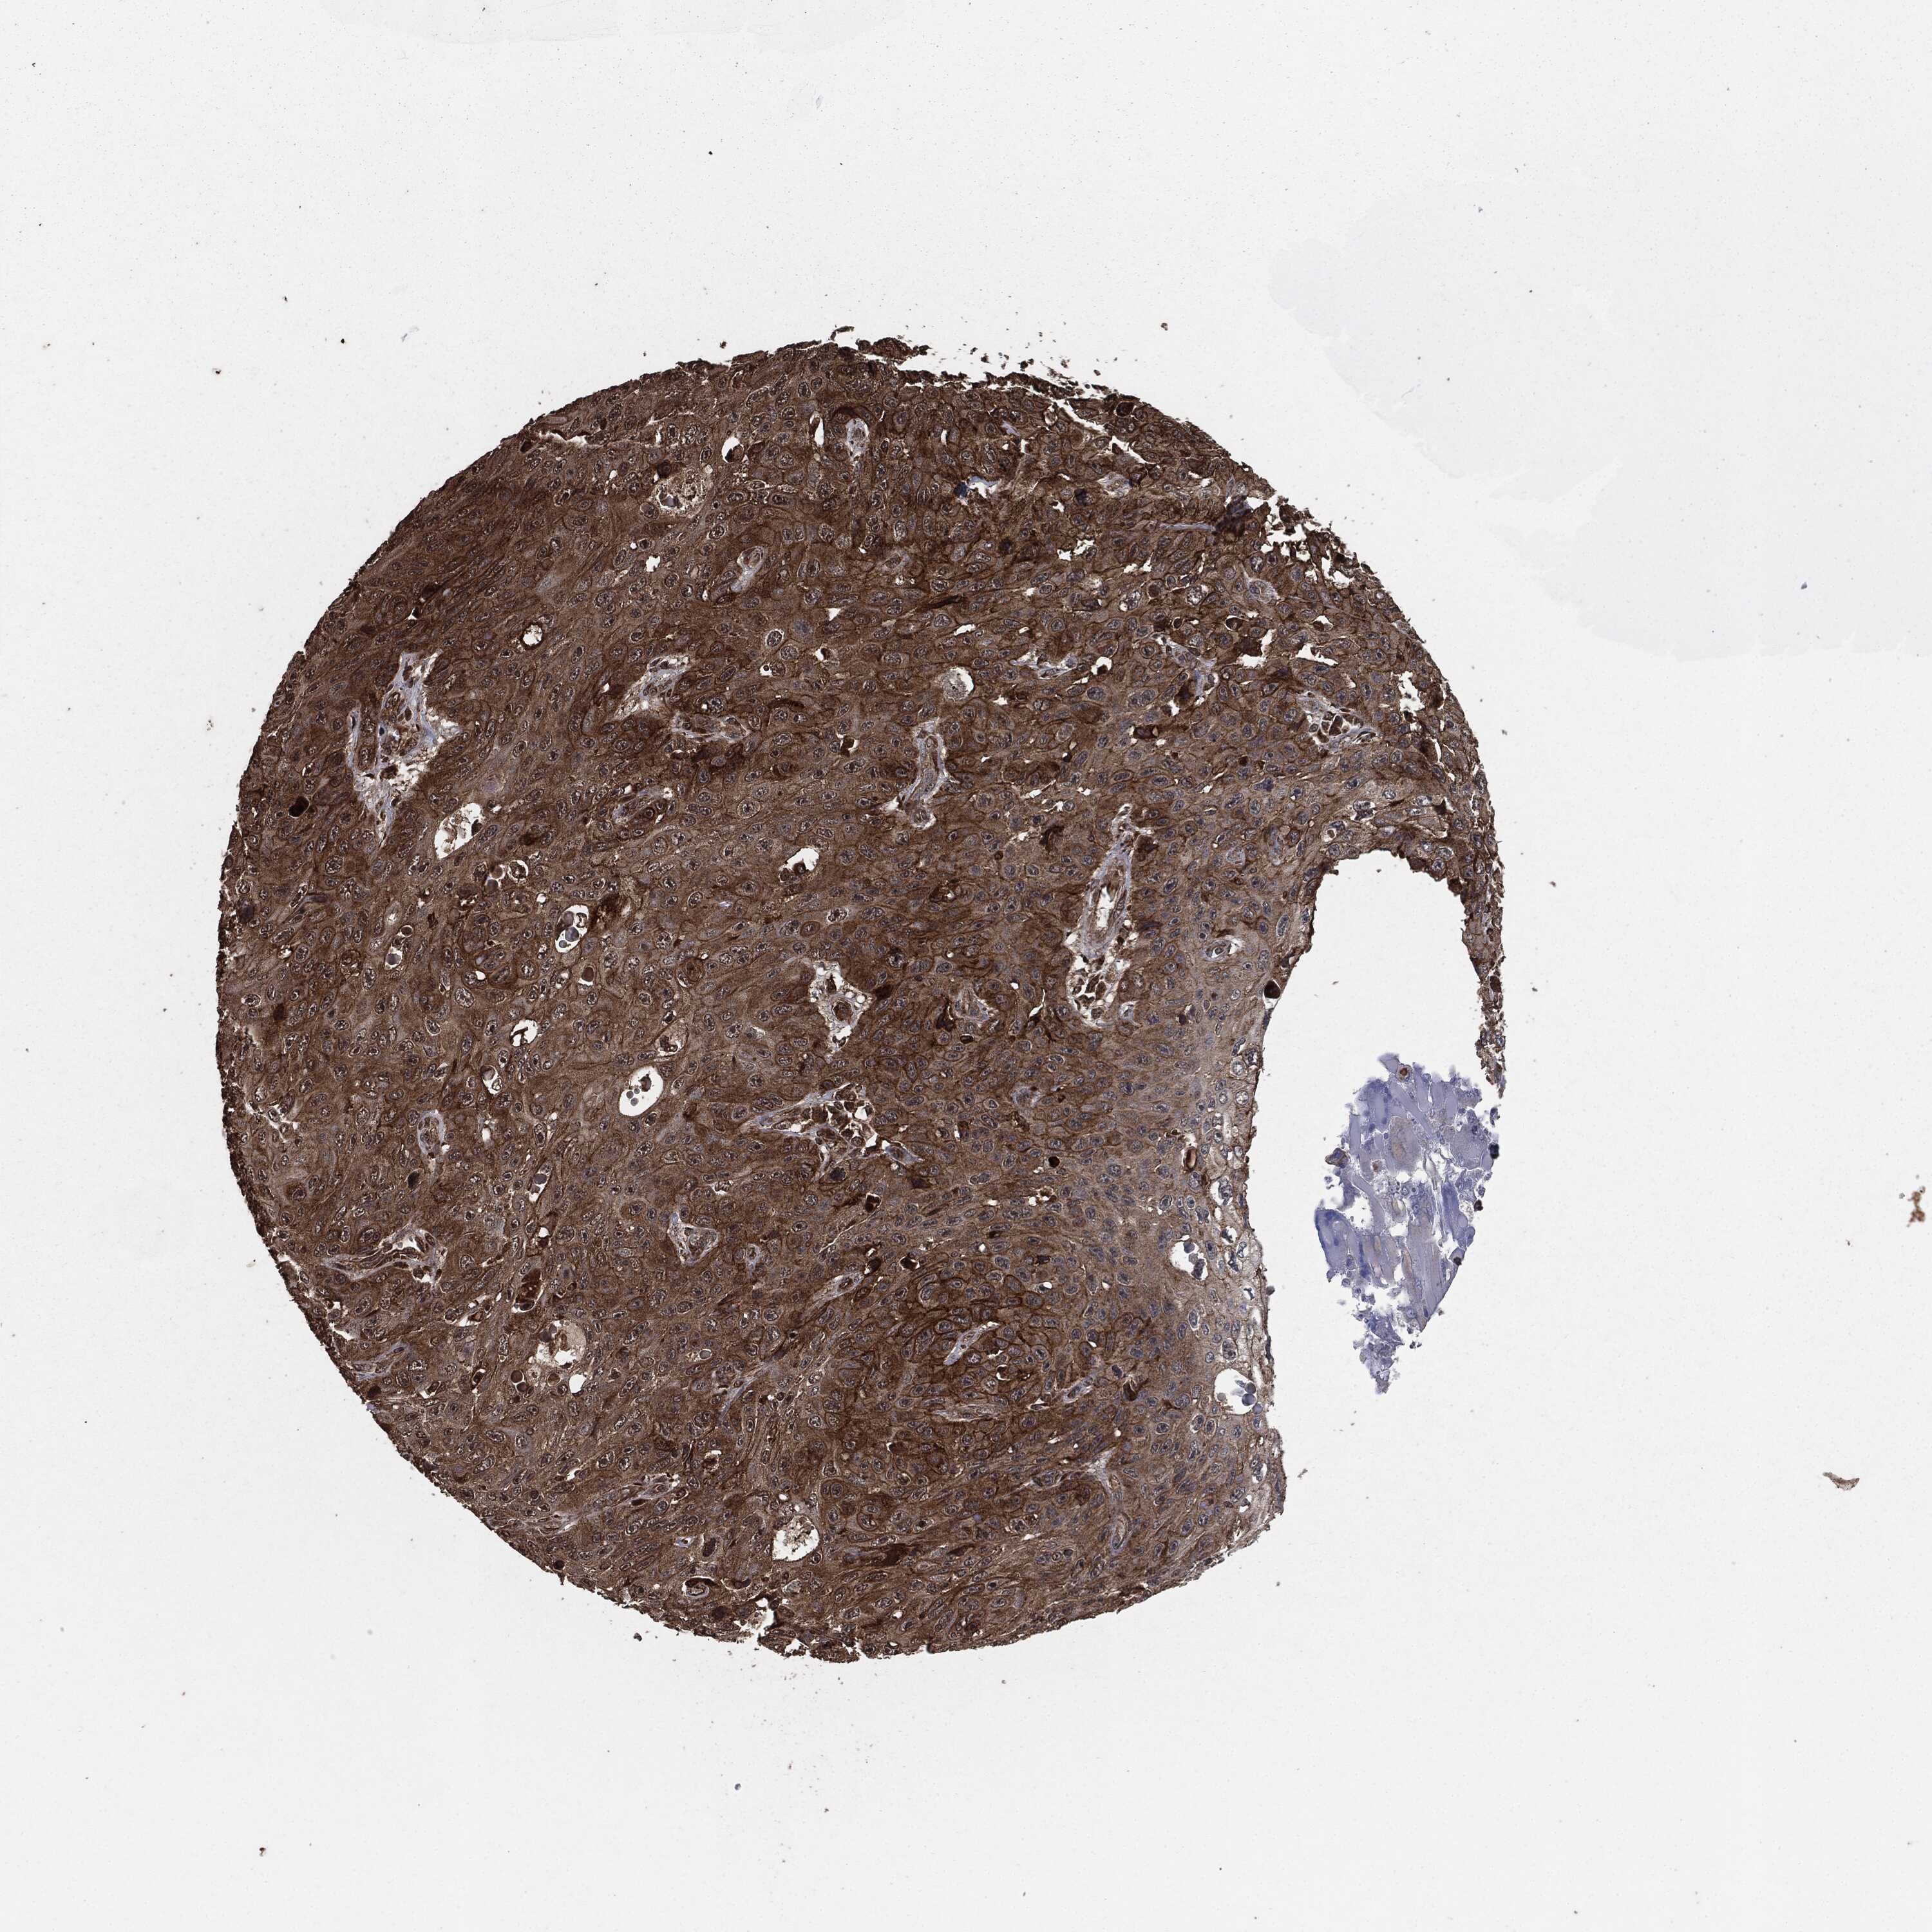

SKIN CANCER - Protein expressioni

A mouse-over function shows sample information and annotation data. Click on an image to view it in a full screen mode. Samples can be filtered based on level of antibody staining by selecting one or several of the following categories: high, medium, low and not detected. The assay and annotation is described here.

Each image is clickable and will lead to virtual microscopy that enables deeper exploration of all samples and also displays staining intensity scores, fraction scores and subcellular localization as well as patient and tissue information for each sample.

HPA001200

Staining

High

Medium

Low

Not detected

Intensity

Strong

Moderate

Weak

Negative

Quantity

>75%

75%-25%

<25%

None

Location

Nuclear

Cytoplasmic/membranous

Cytoplasmic/membranous,nuclear

Squamous cell carcinoma, NOS